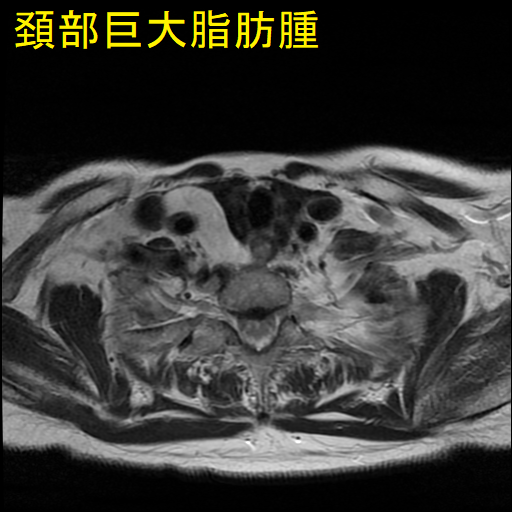

巨大頚部脂肪腫